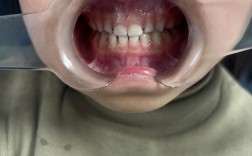

(图片来源网络,侵删)- 压低后牙: 这是最常用的方法,通过特定的矫治器装置(如种植支抗钉、横腭杆、摇椅弓等)施加持续、轻柔的垂直向力,将上颌或下颌的后牙(磨牙和前磨牙)整体压低,这能有效增加下颌前牙区的垂直高度,从而改善深覆合。

- 伸长前牙: 在某些情况下(如下颌后缩伴随深覆合),可能需要有限度地伸长下颌前牙,但这需要非常谨慎,因为过度伸长可能导致前牙开颌、牙周损伤等问题,通常在压低后牙的基础上,配合少量伸长前牙效果更佳。